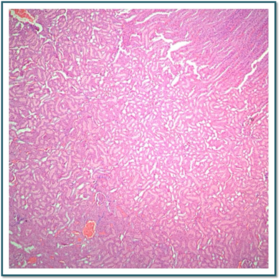

Láminas de Histología

Laboratorio de histología, Bibliografía Ross Pawlina 5ta Edición.